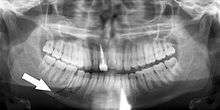

- Impacted wisdom teeth diagnosis and treatment planning - the most common use is to determine the status of wisdom teeth and trauma to the jaws.

Panoramic radiographs have the capability to demonstrate a portion of the neck and display atheromas (calcifications in the carotid artery) which are an indication of both local and generalized (systemic) atherosclerosis. Atherosclerosis of the coronary arteries leading to myocardial infarction (heart attack), and atherosclerosis of the carotid artery leading to stroke are the number one and number three most common causes of death in the United States.[5]

Epidemiology: General Public and High Risk Groups

Additional research projects have further determined the prevalence rate of these atheromas in the general population (3-5%)[7] and among high-risk groups (over 25% in: recent stroke victims,[8] individuals with obstructive sleep apnea syndrome,[9][10] postmenopausal women,[11] type 2 diabetics,[12][13] individuals with dilated cardiomyopathy,[14] and among individuals who have received radiotherapy directed at the neck,[15][16]). These findings have been corroborated by other several other researchers.[17][18][19][20]